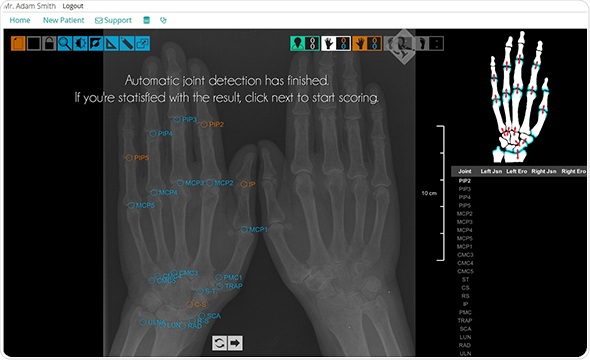

The BGE Bodlnsight product allows the evaluation of X-ray images based on the Sharp/van der Heijde (SvH) scoring system in just a few minutes during the patient diagnosis of rheumatoid arthritis.

The result of several years’ research and development, the BGE BodInsight enables the detailed evaluation (according to the SvH standard) to be performed in everyday medicine. Patients can now get a more detailed evaluation of their X-ray images which leads to better diagnosis and suitable treatment.

The BGE Bodlnsight is a unique solution worldwide and is available online, through a cloud technology. Simply register at www.bgesystems.com to use the product.